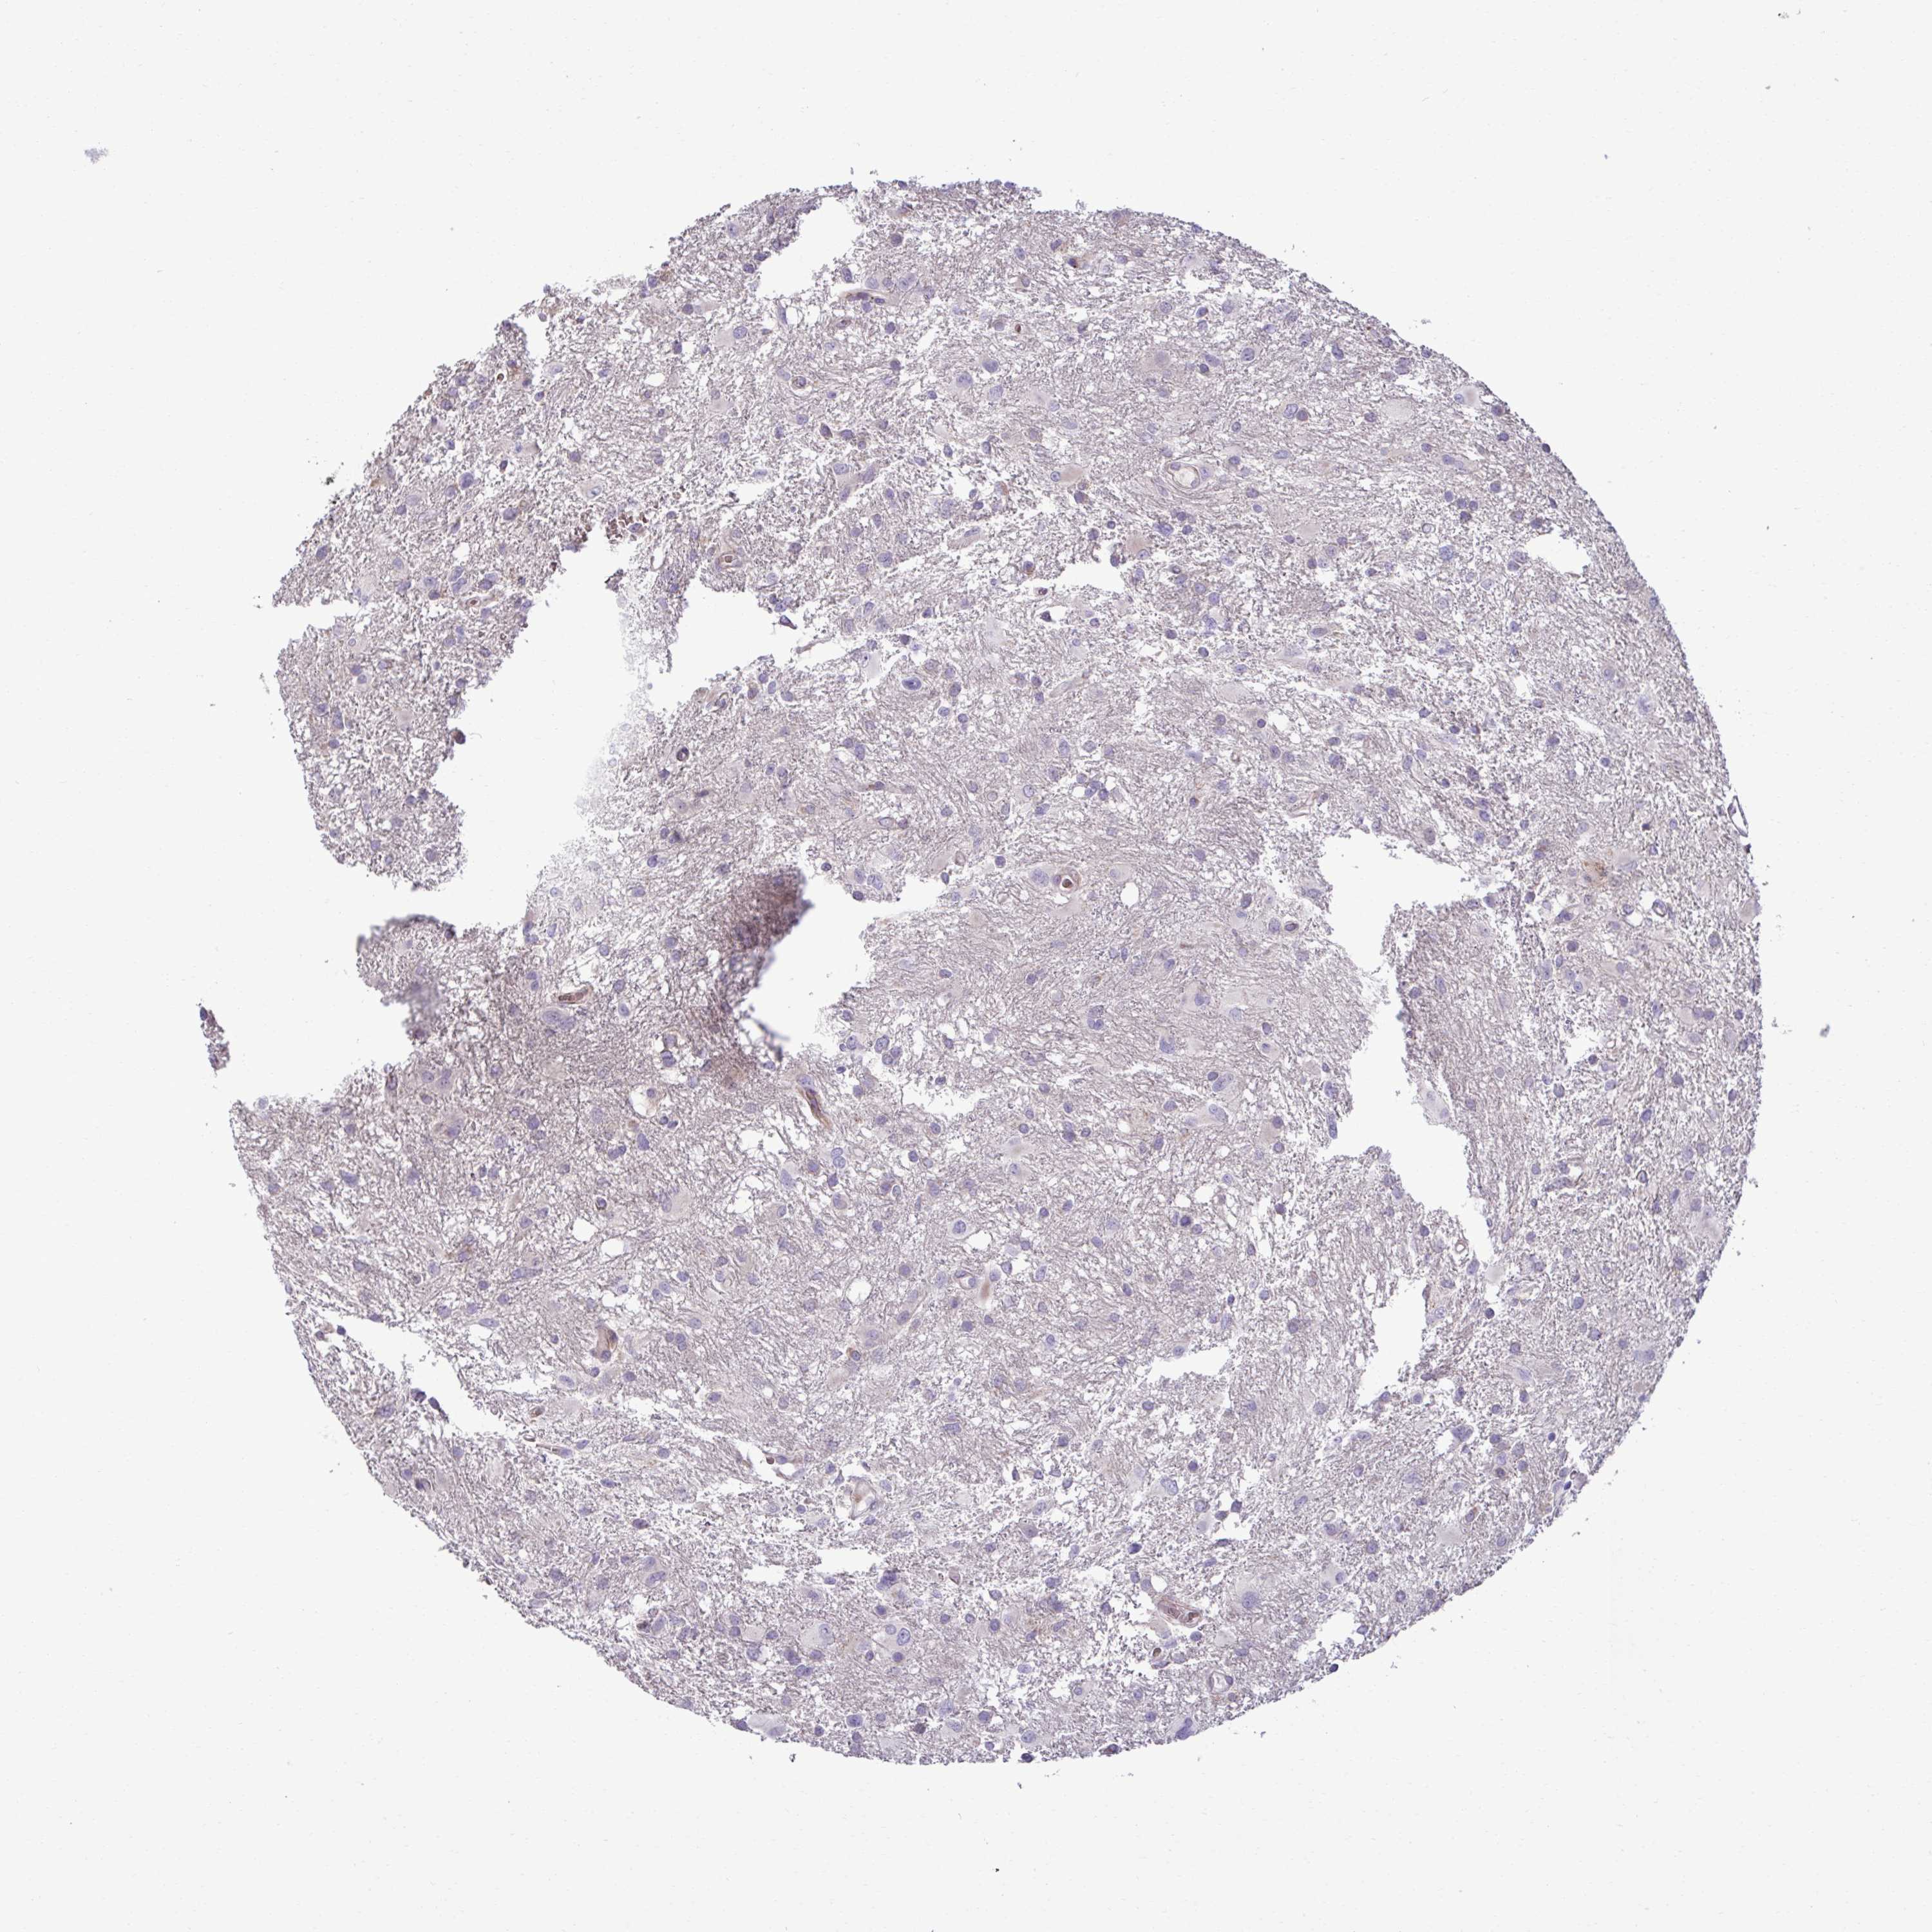

GLIOMA - Protein expressioni

A mouse-over function shows sample information and annotation data. Click on an image to view it in a full screen mode. Samples can be filtered based on level of antibody staining by selecting one or several of the following categories: high, medium, low and not detected. The assay and annotation is described here.

Note that samples used for immunohistochemistry by the Human Protein Atlas do not correspond to samples in the TCGA dataset.

Antibody stainingi

Antibody staining in the annotated cell types in the current human tissue is reported as not detected, low, medium, or high, based on conventional immunohistochemistry profiling in selected tissues. This score is based on the combination of the staining intensity and fraction of stained cells.

Each image is clickable and will lead to virtual microscopy that enables deeper exploration of all samples and also displays staining intensity scores, fraction scores and subcellular localization as well as patient and tissue information for each sample.

Antibody HPA058455

Antibody HPA061230

Staining

High

Medium

Low

Not detected

Intensity

Strong

Moderate

Weak

Negative

Quantity

>75%

75%-25%

<25%

None

Location

Nuclear

Cytoplasmic/membranous

Cytoplasmic/membranous,nuclear

Glioma, malignant, Low grade

Glioma, malignant, High grade